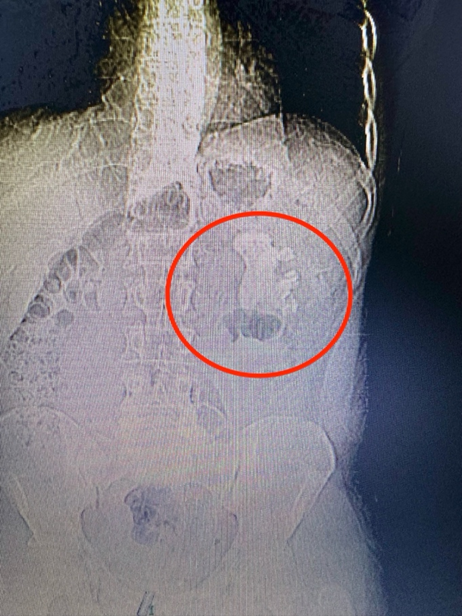

手术经过:郑鑫医生团队在详尽检查和术前评估后,为龚先生实施了经皮肾镜碎石取石手术,在麻醉科的精密配合下,手术非常成功。通过仅一个穿刺通道,医生团队清除了所有结石,实现了患者的完全康复。手术后,龚先生迅速恢复,第二天即撤除造瘘管,第三天顺利出院。

术前与术后复查对比

鹿角型结石是因其形状类似鹿的角而得名,通常由感染性结石组成,填满肾脏内部。传统治疗方法是经皮肾镜碎石取石术,但充满型的鹿角型结石往往需要多通道或多次手术才能彻底清除。鹿角型结石由于其独特的形状和分布,传统上需要多通道或多次手术进行治疗。这类结石通常由感染引起,完全清除对预防复发至关重要。郑鑫医生团队的丰富经验和精湛技艺,单通道手术不仅降低了对肾脏的损害风险,还减少了患者的经济负担。